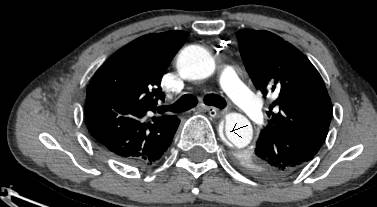

病例五

平扫CT提示主动脉弓层面及右肺动脉层面均可见主动脉血管腔内的内膜片影(红色箭头所示),CTA显示为A型主动脉夹层。